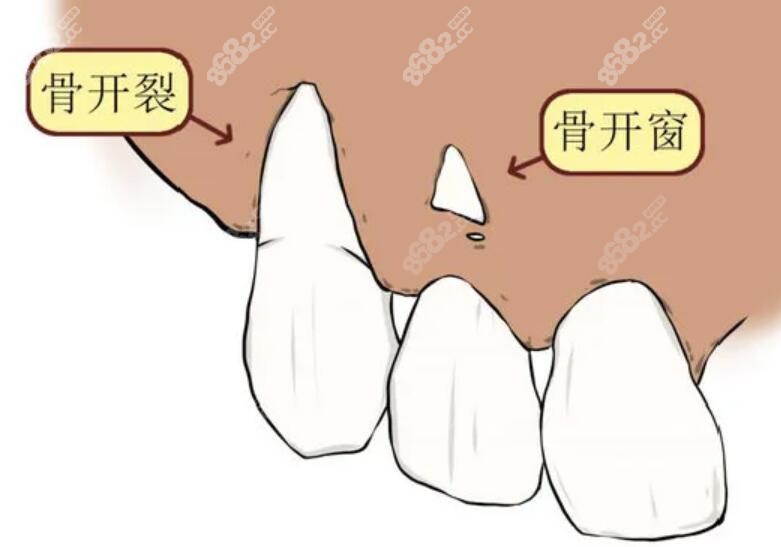

骨开裂和骨开窗图片

骨开窗示意图

正畸形成骨开窗和骨开裂有啥区别?看骨开窗示意图自行判断

骨开窗,骨开裂示意图

正畸形成骨开窗和骨开裂有啥区别?看骨开窗示意图自行判断

骨开窗和骨开裂的对比